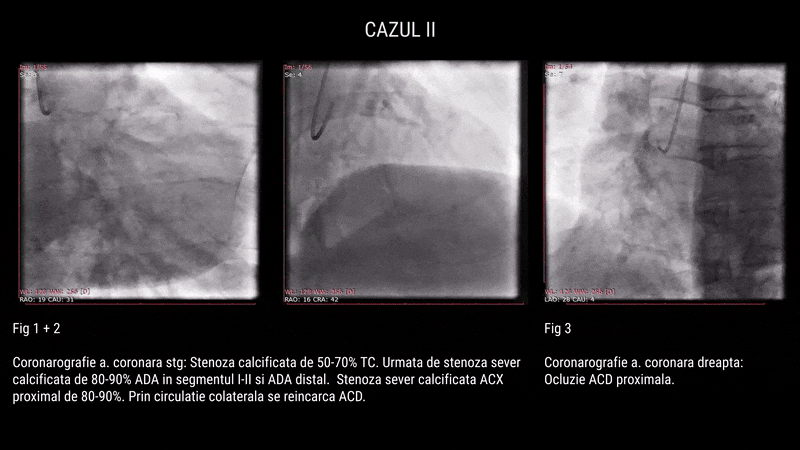

Al doilea caz a fost un pacient de 56 de ani, simptomatic prin angină clasa III și tabagism activ. Examinările au relevat o ocluzie cronică pe LAD II, subocluzie pe ACD II și stenoză semnificativă pe ACX II. Procedura a fost realizată în două etape și a implicat dezobstrucție coronariană cu 9 stenturi DES, utilizarea litotriției intravasculare (Shockwave), tehnica TAP pentru bifurcație și Kissing Balloon.